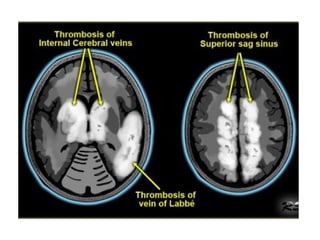

d) Characteristic Patterns of Venous Infarctions:

-There are 3 characteristic patterns of venous

infarctions dependant on the location of the

thrombosed vein :

1-SSS thrombosis : infarction of the parasagittal high

convexity cortex

2-Deep venous system thrombosis : infarction of the

bilateral thalami

3-Transverse sinus thrombosis : infarction of the

posterior temporal lobe

2-Bilateral Infarcts :

-Venous infarcts are often bilateral in the midline and

hemorrhagic

-Occlusion of the midline veins (deep cerebral veins “

Internal cerebral veins and basal veins of Rosenthal

“ , straight sinus & SSS) may result in bilateral areas of

low attenuation on CT and increased T2

-Thrombosis of the deep cerebral veins may involve the

basal ganglia , thalami , midbrain and mesial temporal

lobes in a relatively symmetrical fashion